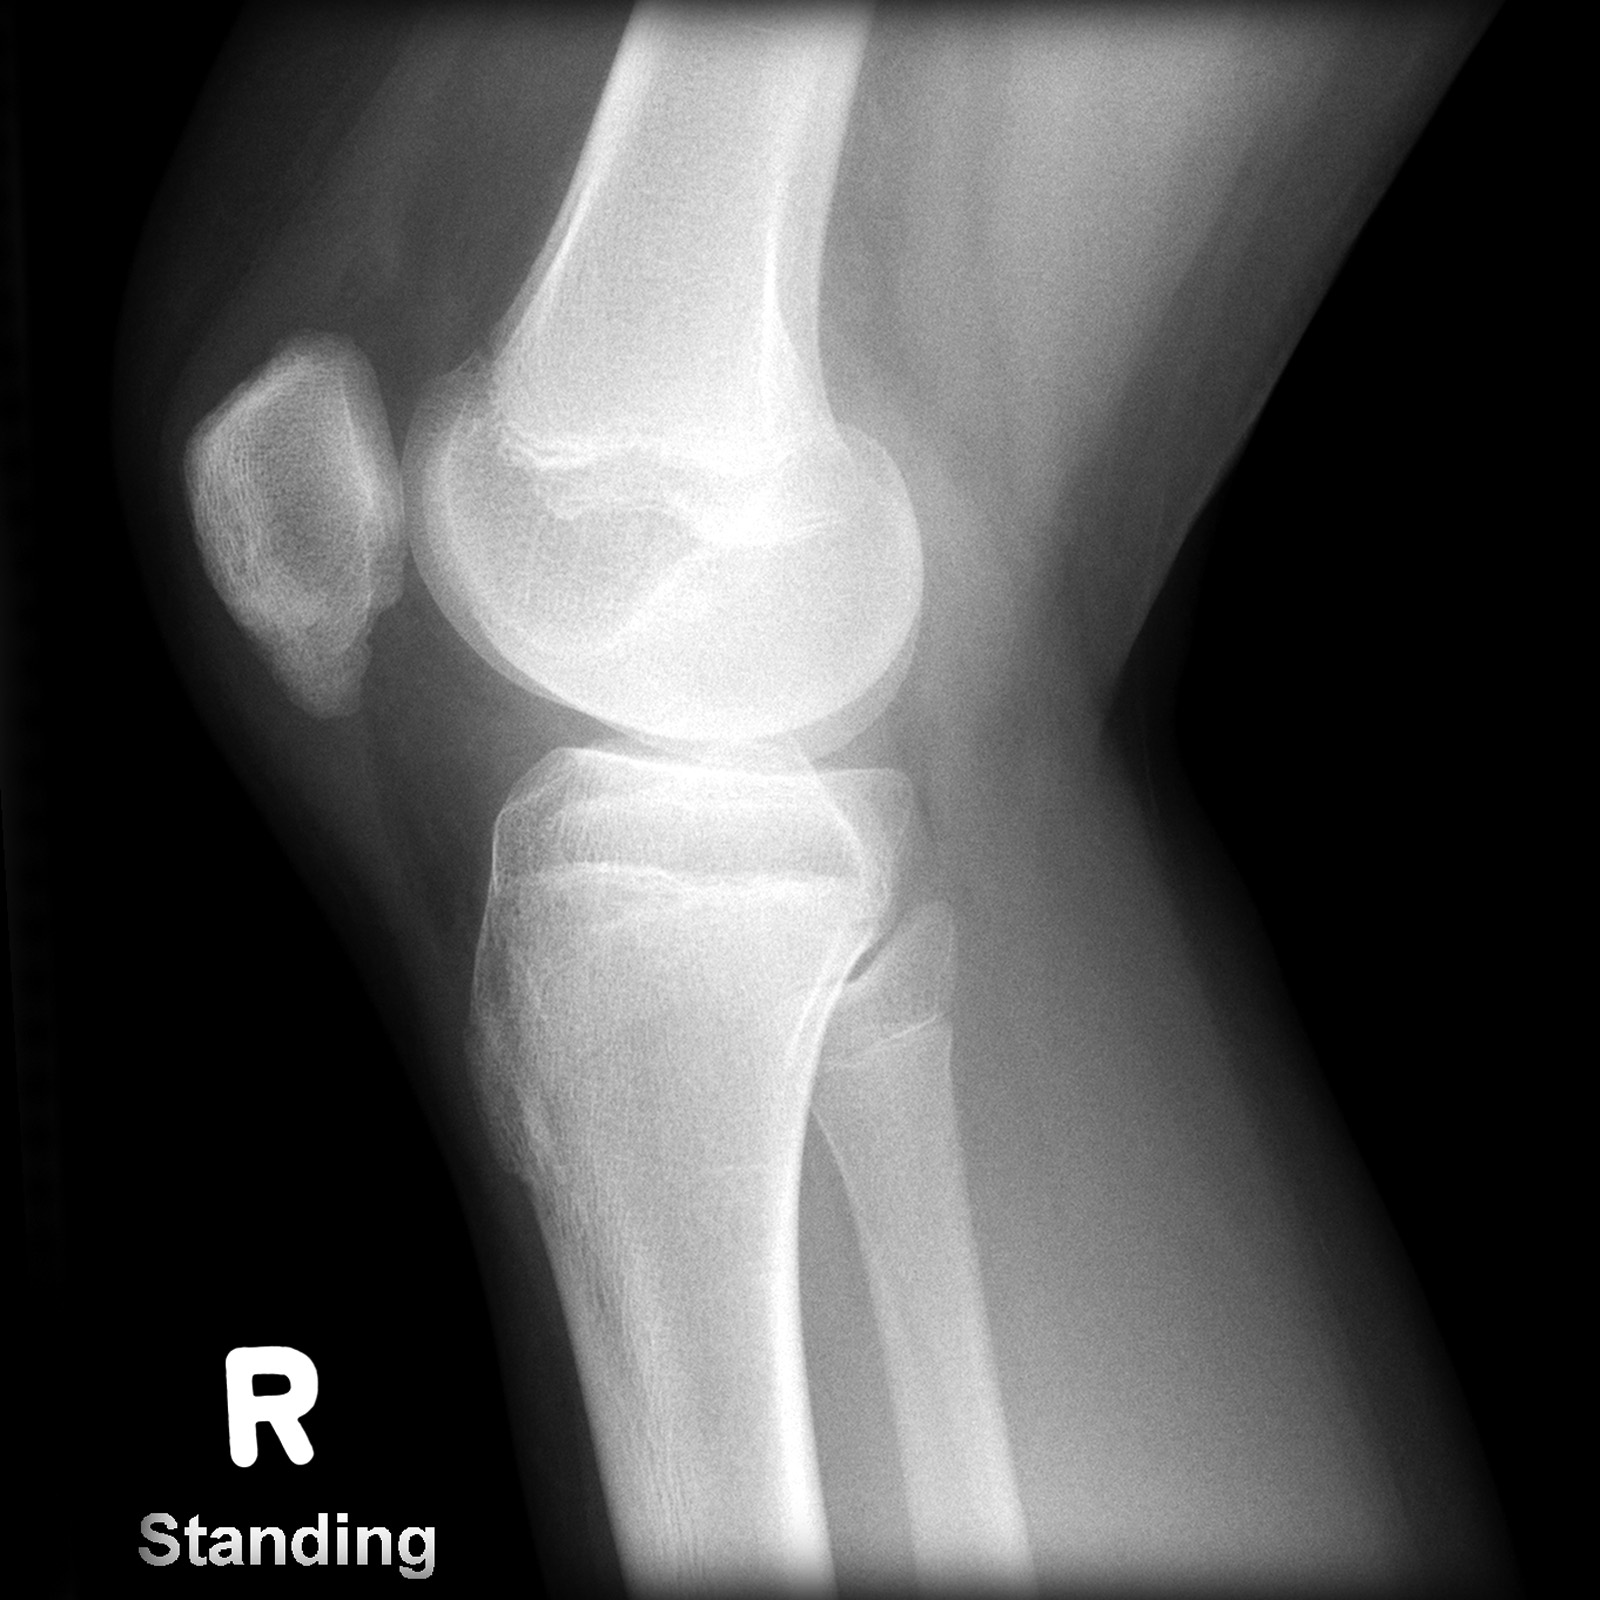

Как и при любой травме коленного сустава для постановки правильного диагноза выполняется рентгенография, на которой-то и можно увидеть перелом. Обычно рентгенографию выполняют в прямой и боковой проекциях, а для диагностики вертикальных переломов выполняют еще и осевую (аксиальную, или Merchant) проекцию.

Прямая (слева) и боковая (справа) проекции, на которых виден горизонтальный перелом надколенника со смещением отломков. Осевая проекция. Вертикальный перелом. Обратите внимание на возникшую в результате смещения ступеньку на скользящей поверхности надколенника.

Осевая проекция. Вертикальный перелом. Обратите внимание на возникшую в результате смещения ступеньку на скользящей поверхности надколенника.Иногда для более точного диагноза могут потребоваться компьютерная и/или магнитно-резонансная томография, но, в подавляющем большинстве случаев, достаточно рентгенографии.

Внешние признаки перелома надколенника имеют ряд характерных особенностей, тем не менее для уточнения диагноза обязательно проводятся рентгенологические исследования. Рентгенологически перелом надколенника особенно хорошо виден на боковом снимке, но в некоторых случаях необходим снимок и в прямой проекции (нога стоит прямо).

Рентгеновские снимки коленной поверхности и профиля будут выполняться систематически. Осевой вид шаровых шарниров в сгибании при 30 ° часто бывает невозможным из-за боли. Эта минимальная рентгенографическая оценка позволяет подтвердить диагноз, указать тип перелома и искать связанные поражения в колене.

Для подтверждения диагноза необходимо выполнить рентгеновские снимки в двух проекциях, иногда требуется выполнение аксиальной проекции, особенно при вертикальных переломах. Обычно, перелом надколенника хорошо виден на рентгеновских снимках.

На рентгенограмме показан перелом тела надколенника без смещения.

На рентгенограмме продемонстрирован перелом нижнего полюса надколенника.

Перелом надколенника слева со смещением отломков. Необходима операция.

Краевой перелом надколенника, хорошо видимый на аксиальной рентгенограмме.